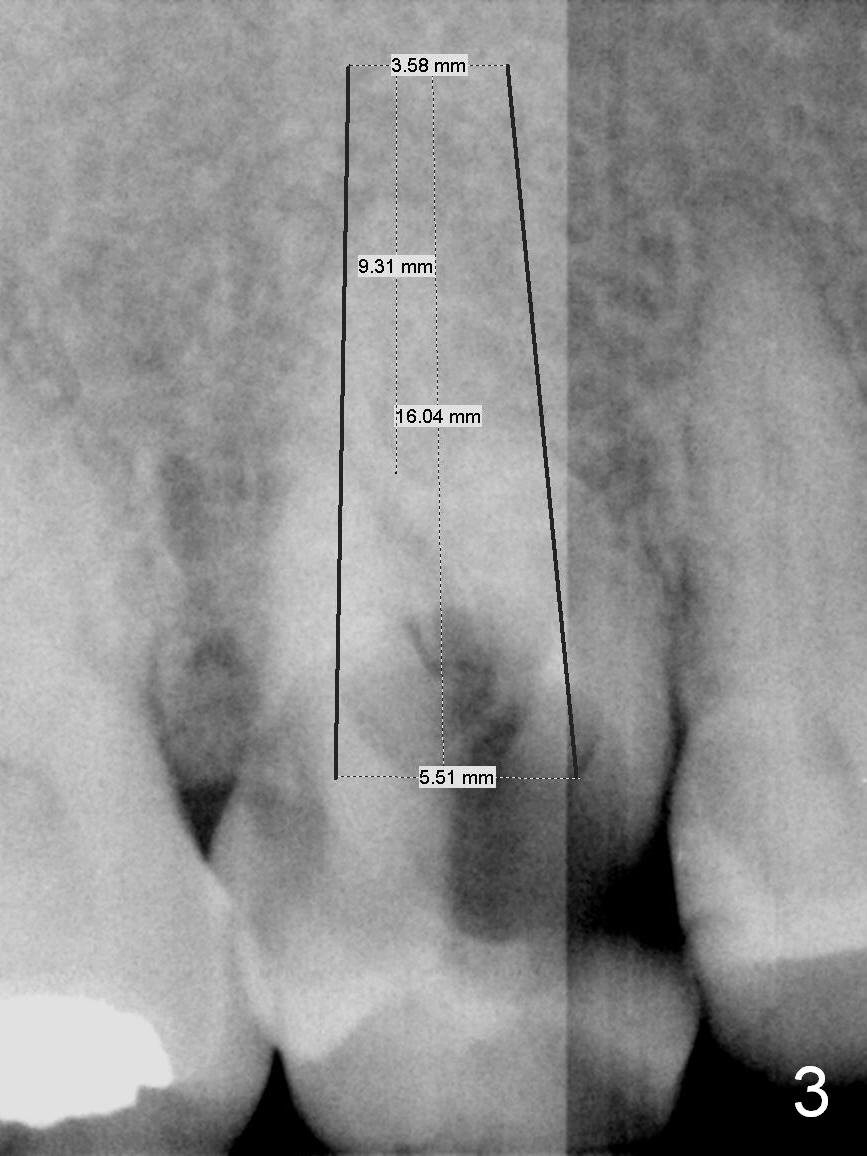

A 52-year-old woman is a dental phobic. Her main concern is the tooth #3 with caries apparently involving the furca (Fig.1 ^). Before extraction, take photos to show a polyp in the pulpal chamber, which is most likely periodontal. After extraction (prepare surgical handpiece, since the tooth most likely fractures at extraction), take photos to show furcal perforation, while the socket is packed with 3 pieces of gauze soaked with Metronidazole. There is apparently sufficient bone apical to the roots (Fig.2). To achieve primary stability, use an implant as long as possible (13 mm of IBS, Fig.3 (implant is drawn to be placed too superficial)) with large diameter appropriate to the septum. The plateau of the implant will be placed apical to the crests and coronal to the septum.